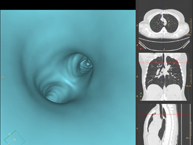

- Broncoscopia virtual

La broncoscopia virtual es una técnica no invasiva que permite la visualización tridimensional y bidimensional de la tráquea y del árbol bronquial mediante la toma secuencial de imágenes captadas con TC Multidetector, obteniendo imágenes bi y tridimensionales. La calidad de las imágenes permite la navegación virtual por el interior de la tráquea y de los bronquios gracias al procesamiento en estaciones de trabajo especializadas.